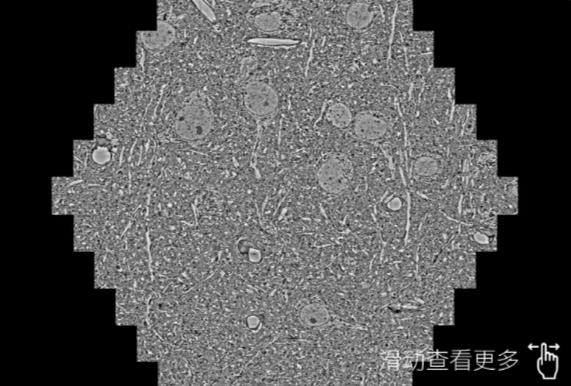

鼠脑切片。左图使用厦门蔡司厦门扫描电镜MultiSEM706对165μmx143pm面积区域成像,耗时仅需1.5秒。右图为鼠脑切片中30μm区域放大效果。样品由芝加哥大学B.Kasthuri提供。

使用蔡司高速厦门扫描电镜MultiSEM对1mm²人脑皮层组织进行高分辨成像,并对其中的各种细胞结构进行三维重构分析。左图展示了2x3mm²组织平面中锥体神经元的三维重构效果。右图显示了局部体积神经元三维重构。图像由哈佛大学chtman实验室提供,渲染图由D. Berger 制作。